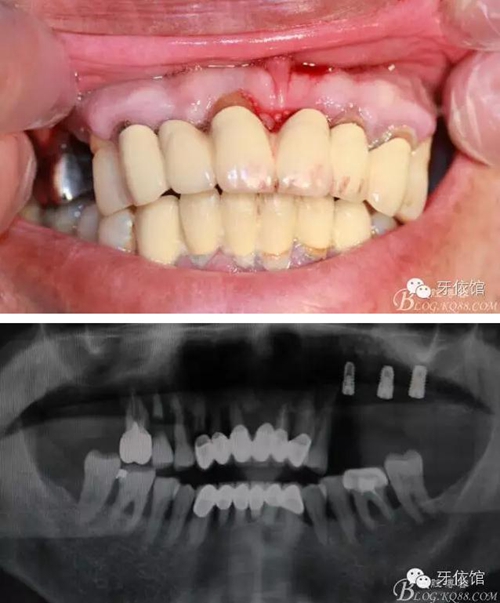

患者男,65歲,口內(nèi)多組烤瓷橋,具體時(shí)間不詳,左上5,6,7已于5個(gè)月前即可種植,OSS-TEM系統(tǒng),余留牙都已三度松動(dòng);此患者笑線高,微笑時(shí)唇緣在齦緣上4mm。

術(shù)前口內(nèi)照和X光片